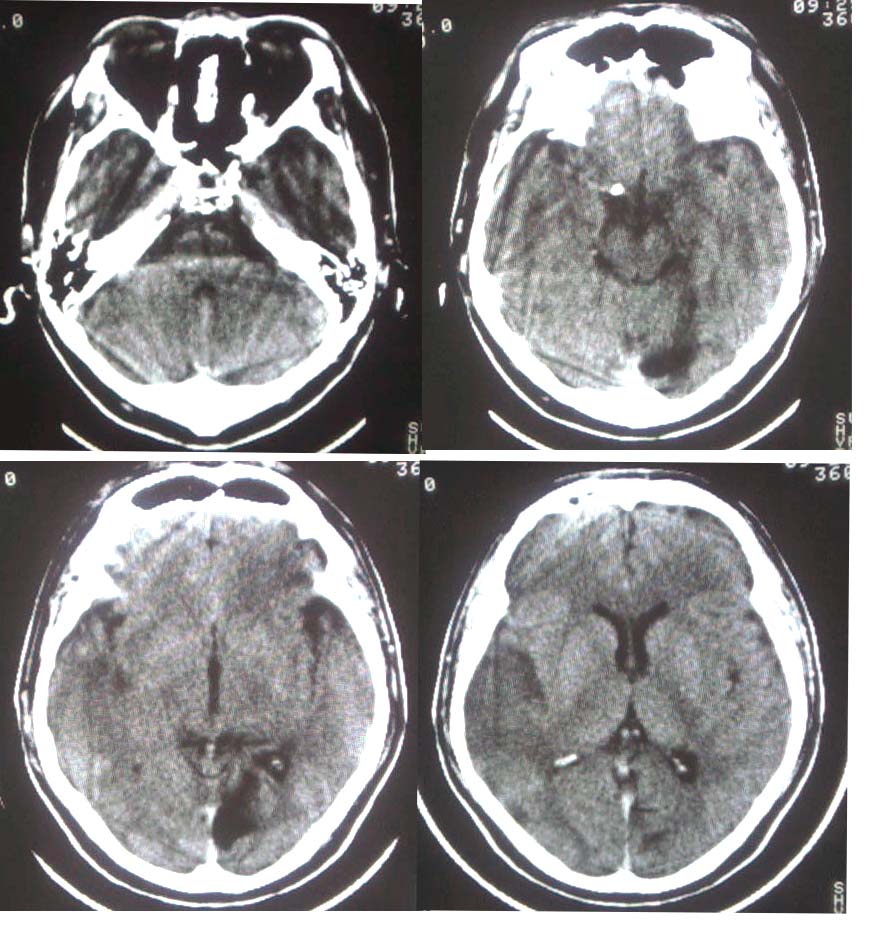

这是一个49岁 男性患者,近两天头痛,自感言语不利。既往有脑梗塞病使。麻烦各位老师看看有没有新的病灶。谢谢!

是新发病灶,另外左枕叶可见软化灶形成.

是新发病灶,另外左枕叶可见软化灶形成